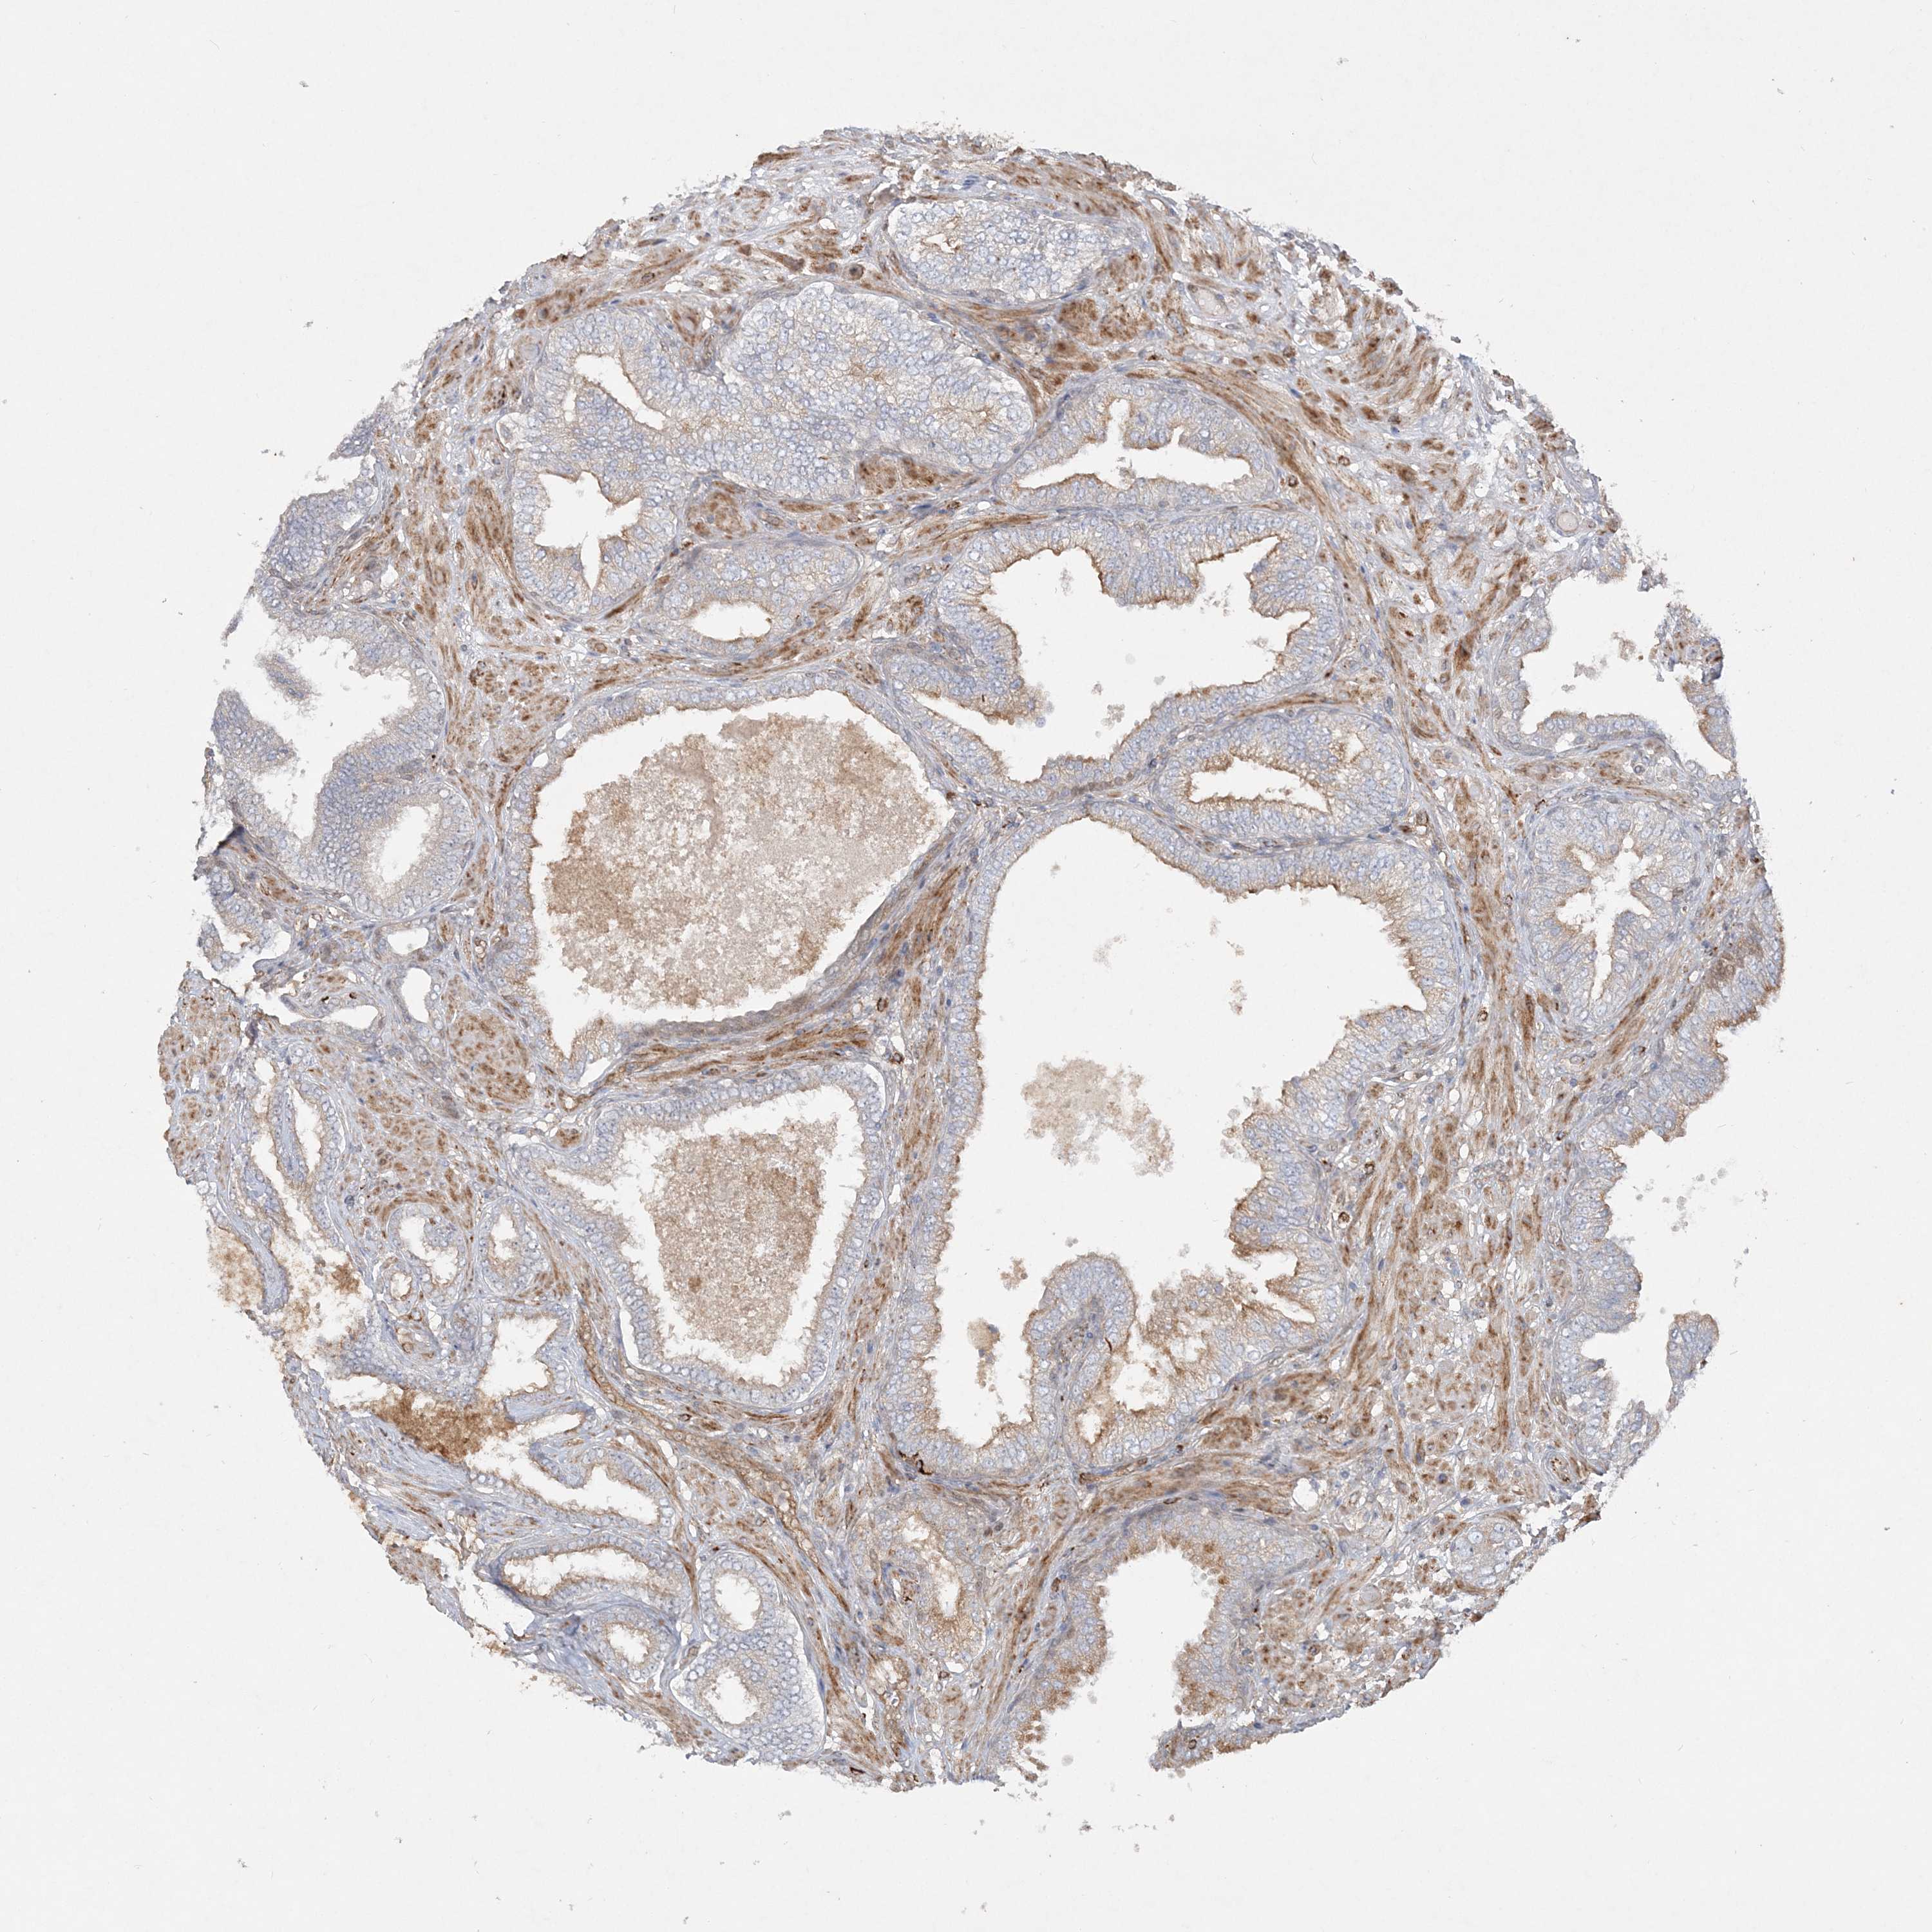

PROSTATE CANCER - Protein expressioni

A mouse-over function shows sample information and annotation data. Click on an image to view it in a full screen mode. Samples can be filtered based on level of antibody staining by selecting one or several of the following categories: high, medium, low and not detected. The assay and annotation is described here.

Antibody stainingi

Antibody staining in the annotated cell types in the current human tissue is reported as not detected, low, medium, or high, based on conventional immunohistochemistry profiling in selected tissues. This score is based on the combination of the staining intensity and fraction of stained cells.

Each image is clickable and will lead to virtual microscopy that enables deeper exploration of all samples and also displays staining intensity scores, fraction scores and subcellular localization as well as patient and tissue information for each sample.

Antibody HPA036698

Antibody HPA036699

Staining

High

Medium

Low

Not detected

Intensity

Strong

Moderate

Weak

Negative

Quantity

>75%

75%-25%

<25%

None

Location

Nuclear

Cytoplasmic/membranous

Cytoplasmic/membranous,nuclear

Adenocarcinoma, High grade

Adenocarcinoma, Low grade